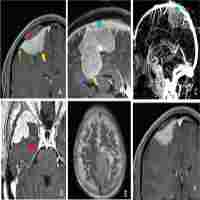

| Abstract | Purpose: The purpose was to explore the correlation between hematological parameters and the progression of WHO grade II meningioma, and establish a clinical prognostic model based on hematological parameters and clinical prognostic factors to predict the progression-free survival (PFS) of patients. Methods: A total of 274 patients with WHO grade II meningiomas were included. Patients were randomly divided into a training cohort (192, 70%) and a test cohort (82, 30%). In the training cohort, the least absolute shrinkage and selection operator Cox regression analysis was used to screen for hematological parameters with prognostic value, and the hematological risk model (HRM) was constructed based on these parameters; univariate and multivariate Cox regression analyses were utilized to screen for clinical prognostic factors, and a clinical prognostic model was constructed based on clinical prognostic factors and HRM. The prognostic stability and accuracy of the HRM and clinical prognostic model were verified in the test cohort. Subgroup analysis was performed according to the patients’ different clinical characteristics. Results: Preoperative neutrophil-to-lymphocyte ratio, lymphocyte-to-monocyte ratio, platelet-to-lymphocyte ratio, albumin-to-globulin ratio, D-dimer, fibrinogen, and lactate dehydrogenase were associated with the PFS of patients. The areas under curve of the HRM were 0.773 (95% confidence interval [CI] 0.707-0.839) and 0.745 (95%CI 0.637-0.852) in the training cohort and test cohort, respectively. The progression risk was higher in the high-risk group than that in the low-risk group categorized by the optimal cut-off value (2.05) of hematological risk scores. The HRM, age, tumor location, tumor size, peritumoral edema, extent of resection, Ki-67 index, and postoperative radiotherapy were the prognostic factors for the progression of meningiomas. The corrected C-index of the clinical prognosis model was 0.79 in the training cohort. Clinical decision analysis showed that the clinical prognostic model could be used to obtain favorable clinical benefits. In the subgroup analysis, the HRM displayed excellent prognostic stability and general applicability in different subgroups. Conclusions: Preoperative hematological parameters are associated with the postoperative progression of WHO grade II meningiomas. The clinical prognosis model constructed based on hematological parameters and clinical prognostic factors has favorable predictive accuracy and clinical benefits. |